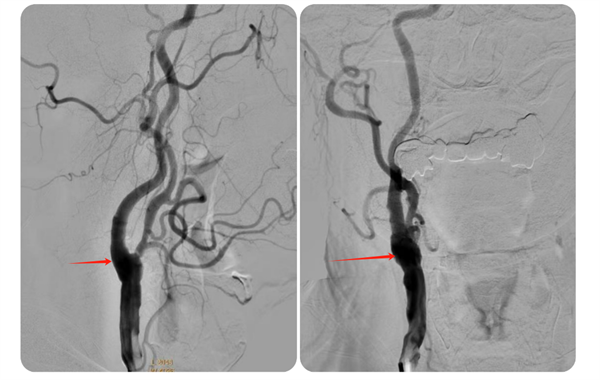

近日,皇冠足球投注网 神经外科收治了一名74岁高龄且伴有多年高血压、糖尿病史的高危患者何先生(化名)。何先生此前已接受过右侧椎动脉、左侧锁骨下动脉支架植入术,但近期因头晕、左侧肢体乏力等症状再次入院。经过详细检查,医生发现何先生右侧颈内动脉起始部存在重度狭窄,狭窄率高达75%,情况危急。

▲术前脑血管造影

术后,何先生顺利苏醒,回到神经外科病房进行监护治疗,术后7天伤口愈合良好拆线出院。8月何先生来皇冠足球投注网 复查,DSA检查提示右侧颈动脉狭窄已完全恢复并无再狭窄,头晕及左侧肢体乏力症状也完全缓解了。

▲术后狭窄完全解除